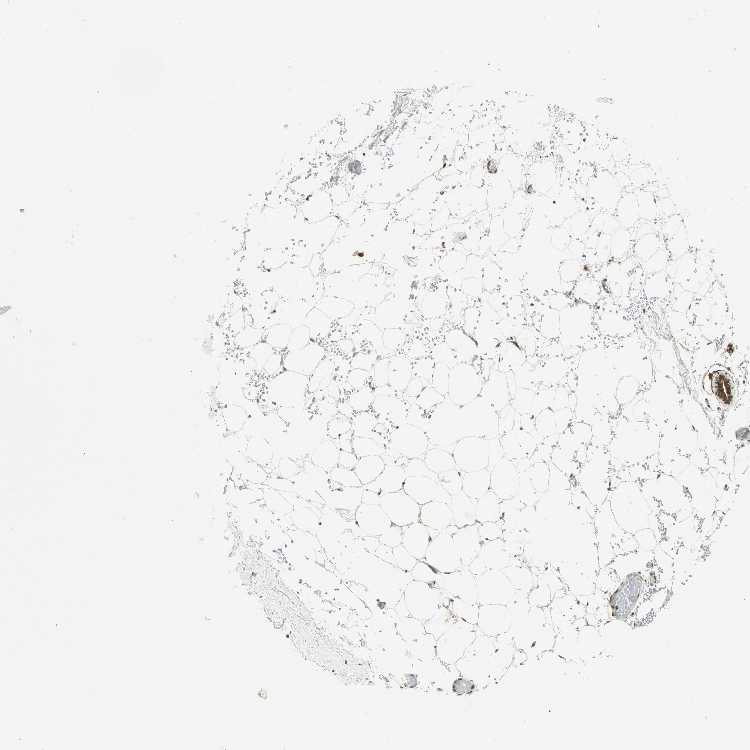

BREAST - Antibody stainingi

Antibody staining in the annotated cell types in the current human tissue is reported as not detected, low, medium, or high, based on conventional immunohistochemistry profiling in selected tissues. This score is based on the combination of the staining intensity and fraction of stained cells.

Each image is clickable and will lead to virtual microscopy that enables deeper exploration of all samples and also displays staining intensity scores, fraction scores and subcellular localization as well as patient and tissue information for each sample.

Antibody HPA003162Antibody CAB005191

Adipocytes MediumMedium

Glandular cells MediumHigh

Myoepithelial cells MediumHigh